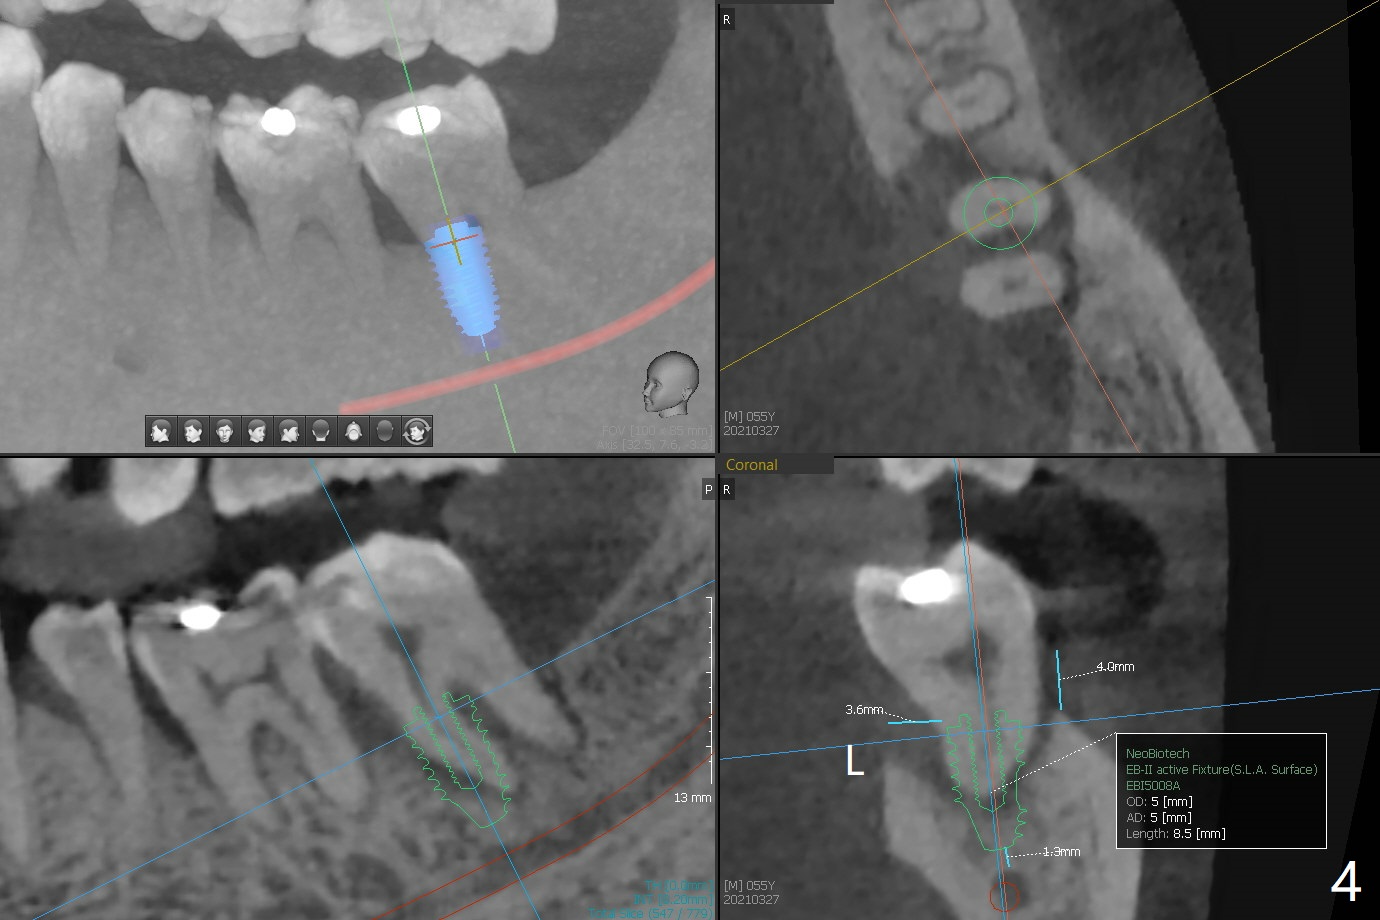

55岁男13年前就诊深洗同时拔除左下智齿(第二第三磨牙之间无骨,图一),拔除后没有植骨。十年后第二磨牙远中出现骨缺损(图二),十三年后第二磨牙松动(图三),需要拔除种植(图四)。其实当年拔除后必须植骨(图一’:红色 (白色:膜或者塞)),甚至种植(图一”:绿色),植骨。Thirteen years post #17 extraction, the lingual plate (L) is lower than the buccal one (B). Return to Prevent Molar Periimplantitis (Protocols, Table) No Caries No Antibiotic Plug 提升 手术 Xin Wei, DDS, PhD, MS 1st edition 03/27/2021, last revision 05/31/2021